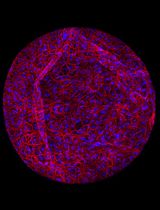

Development, Expansion, and Histological Characterization of Patient-Derived Liver Organoids for Drug Screening and Disease Modeling

SD Silvia De Siervi

SM Stefania Mantovani

BO Barbara Oliviero

MM Mario U. Mondelli

MD Martina Di Noia

CS Cristiana Soldani

BF Barbara Franceschini

Fabrizio De Luca Fabrizio De Luca

MM Marcello Maestri

SC Salvatore Corallo

ML Marco Lolicato

SC Stefania Cannito

CT Cristian Turato

79 Views

Mar 5, 2026

Organoids are self-organizing 3D tissues representing an innovative technology with interesting implications and potential for the study of tumor biology. They can be developed from fine-needle biopsies or resection material from healthy or tumor tissues. Patient-derived organoids are able to retain most of the histological characteristics, the expression profile, and the genomic landscape of the corresponding primary tissues, making them suitable for translational studies and for the identification of molecular alterations in the field of personalized medicine. Here, we describe a detailed protocol for the preparation and in vitro expansion of tumor and non-tumor organoids from surgical resections or needle biopsies of patients with hepatocellular carcinoma (HCC) and intrahepatic cholangiocarcinoma (iCCA), enabling subsequent testing of small-molecule VDAC1 antagonists at different doses. In parallel, we developed a hepatic steatosis model by treating healthy liver organoids with oleic acid, recapitulating key features of lipid accumulation and metabolic dysfunction in vitro. This protocol enables the generation of patient-derived liver organoids that preserve the histological and molecular characteristics of their original tissue, providing a robust and versatile platform for translational studies, personalized drug testing, and the exploration of novel therapeutic strategies targeting tumor metabolism.